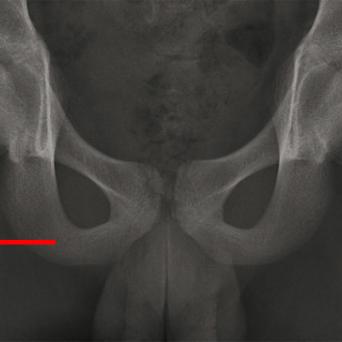

L’image

du jour